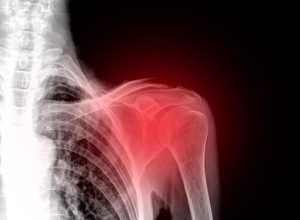

कंधे का दर्द एक बहुत ही असुविधाजनक और अक्षम कर देने वाली स्थिति है। कंधे के जोड़ से ही आप अपने चारों ओर के वातावरण के साथ कुशलतापूर्वक सामंजस्य स्थापित कर सकते हैं। कई प्रकार की चोटें होती हैं जो कंधे के दर्द, सूजन और गतिहीनता का कारण बन सकती हैं। साथ ही, यदि सही ट्रीटमेंट उपचार ना किया जाए तो सूजन लंबे समय तक चल सकती है।

सबसे पहले यह जान लेना जरूरी है कि कंधे का दर्द एक बहुत ही आम समस्या है। अस्थिभंग या हड्डी टूट जाने के मामलों में आपको डॉक्टर की राय लेनी होगी।